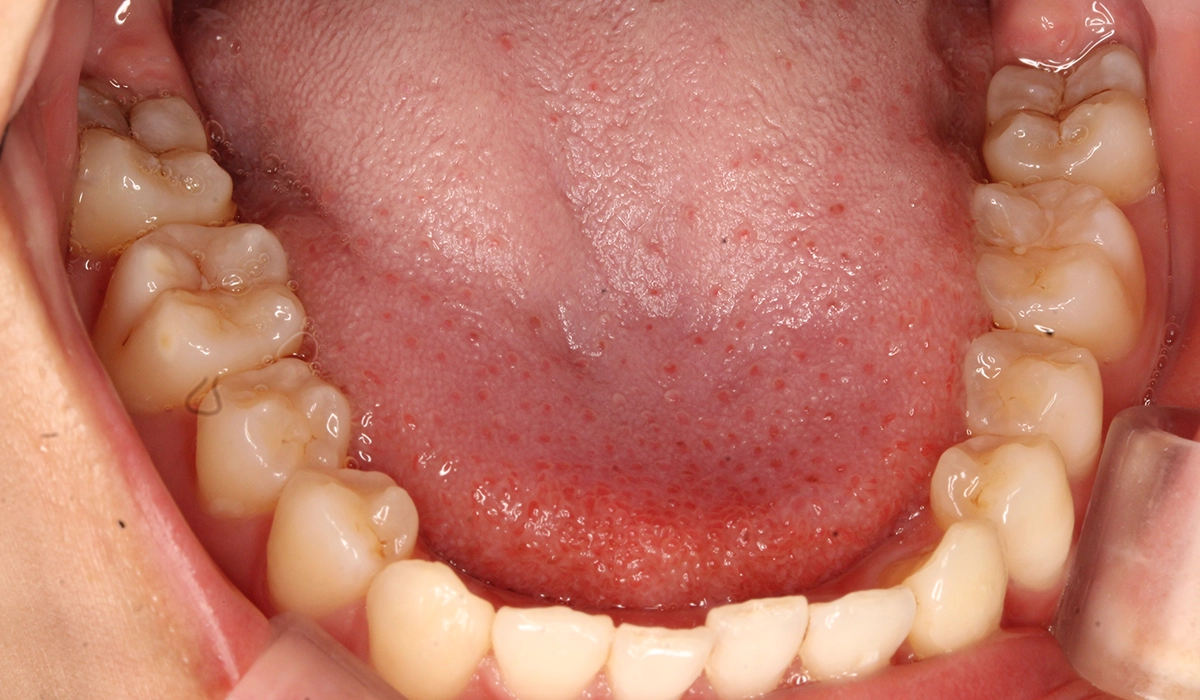

術前:下顎

術後:下顎